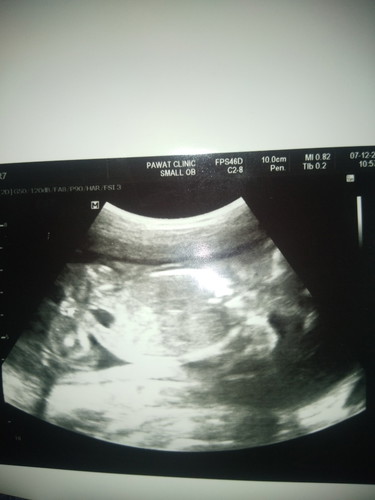

คุณแม่บ้านอื่นช่วยดูให้เค้าทีคะ ว่า แบบนี้ผู้หญิงหรือชายคะ

ภาพไม่บอกเพศคะคุณแม่

ภาพไม่บอกเพศจ้า